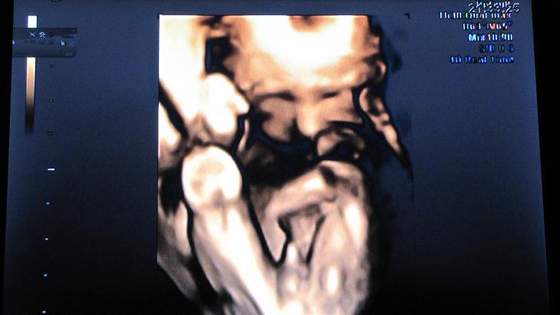

to ja pokaze swojego :-):-):-)

Na wizycie ok, mała waży 1150 :-)

Szyjka się nie skraca i jest zamknięta. W wolnej chwili wkleje foto ;-)

Już po wizycie Dzidziuś nadal jest chłopcem waż 1387g. Szyjka twarda i zamknięta więc wszystko jest OK![]()

Mamy juz kilku czerwcowych Filipkow:-)Hej dziewczynki....Byłam dziś na wizycie.Szyjka stanęła w miejscu na 3.9cmWiec nie musze już tak duzo polegiwać :-) Mały nadal jest Filipkiem i waży 1019gr :-)Teraz powinien przybierać ponad 100gr tyg więc na kolejnej wizycie za 3 tyg sprawdzimy czy mimo tej mojej astmy przyrost wagi jest prawidłowy.